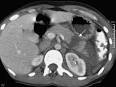

Scanner abdominal